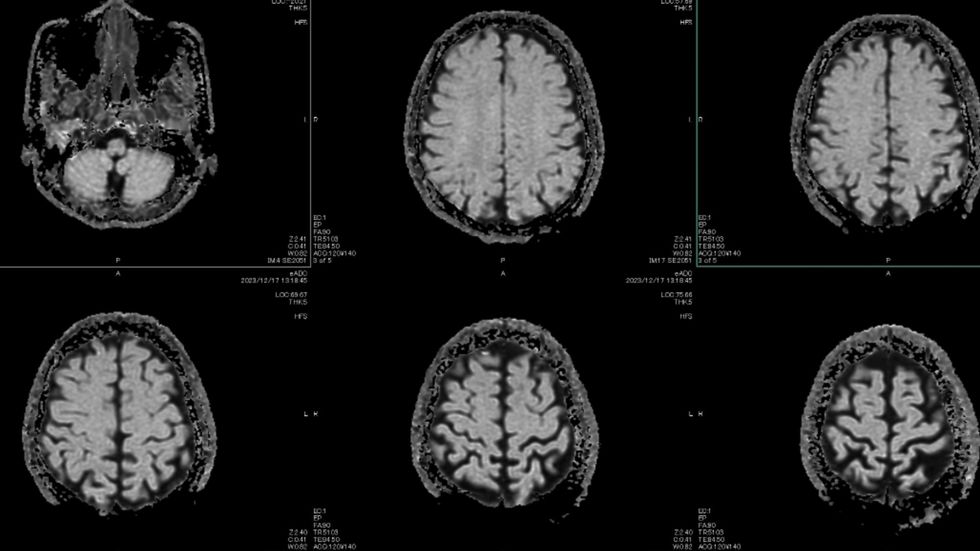

Habits like reading could help prevent or delay dementia

|GETTY

Regularly engaging in mentally stimulating activities could delay brain decline by 6 years